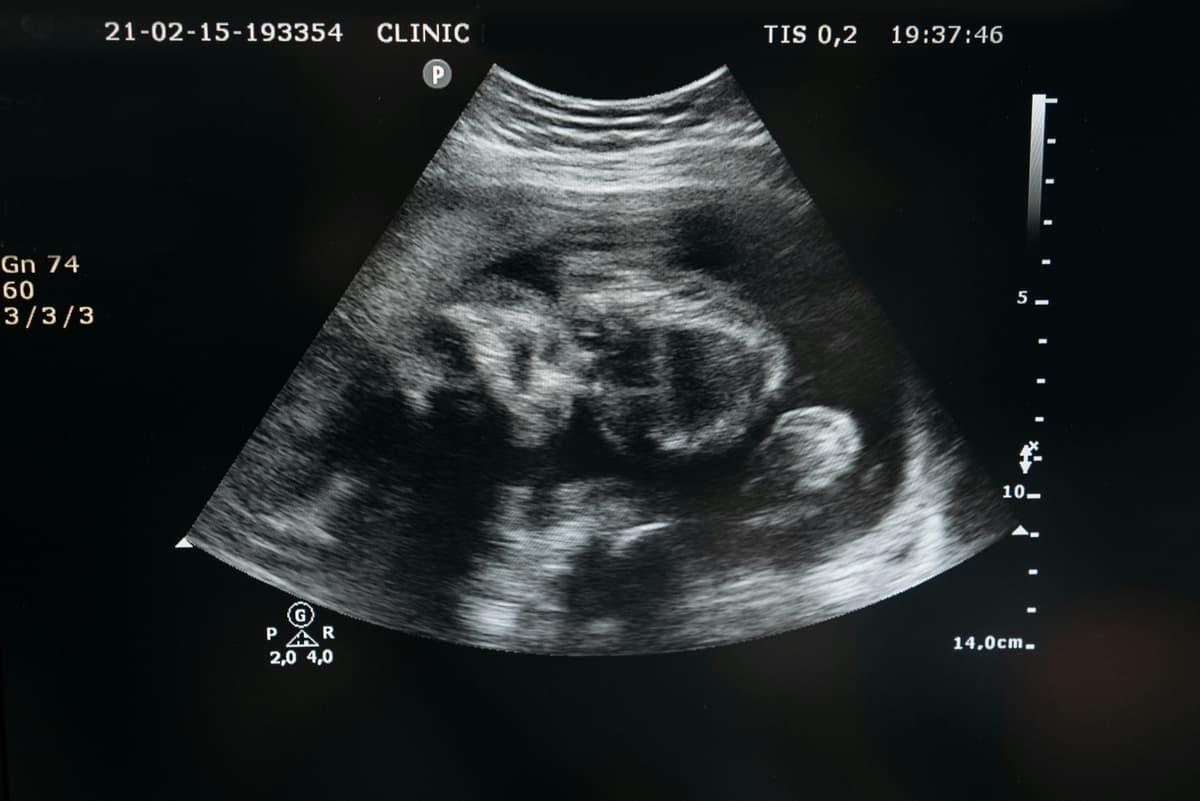

Ultrasound – Safe and non-invasive imaging for soft tissues, blood flow, and internal organs.